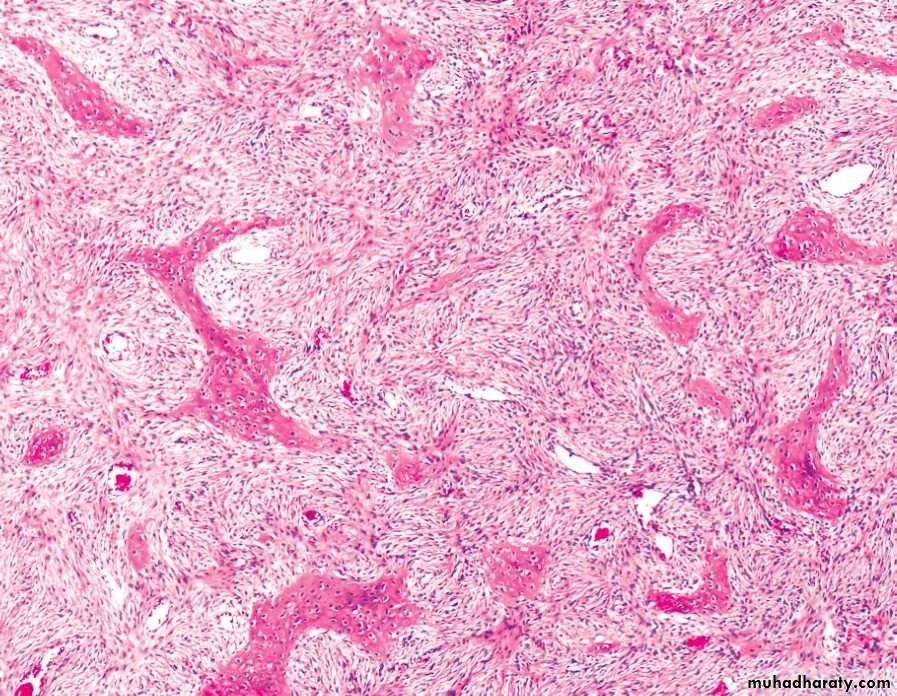

FD showing irregular trabecullae (C-shaped or Chinese characters shaped trabaculae, (described as "Chinese letters“) which are usually coarse woven bone, are seen instead of well-organized lamellar bone. with compact stroma of interlacing collagen fibers